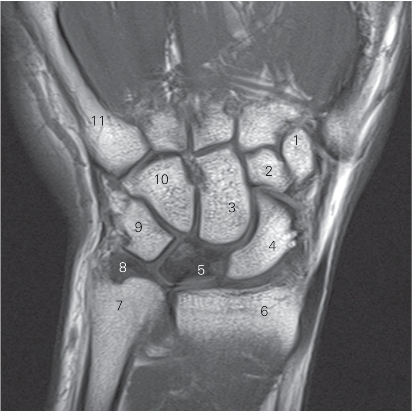

图4-55 经下尺桡关节的冠状断层MR T1加权图像

1 小多角骨 trapezoid bone 2 头状骨 capitate bone

3 舟骨 scaphoid bone 4 舟月韧带 scapholunate ligament

5 下尺桡关节 distal radioulnar joint 6 桡骨 radius

7 尺骨 ulna

8 三角纤维软骨 triangular fibrocartilage

9 月三角韧带 lunatotriquetral ligament 10 三角骨 triquetral bone

11 钩骨 hamate bone